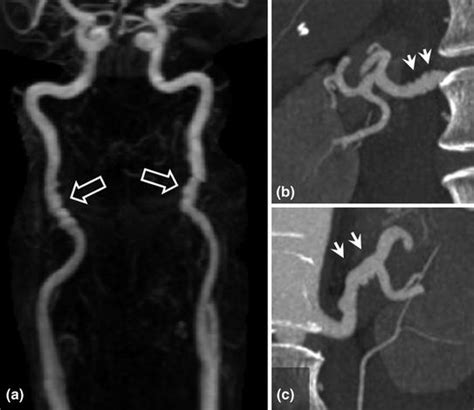

Incidental findings in PSEI scans are, at their core, unexpected discoveries. Think of it like this: you go in for a scan specifically to check your prostate (thanks, PSA !), and BAM! The scan picks up something else entirely – maybe a small kidney stone, or a tiny spot on your liver. These aren’t related to your prostate health, but they showed up on the image anyway. Because PSEI scans are designed to visualize the prostate gland with high precision, they also capture images of surrounding areas, including the bladder, seminal vesicles, pelvic bones, and sometimes even parts of the lower abdomen. Consequently, abnormalities in these regions might be detected unexpectedly, leading to what we call incidental findings . The prevalence of incidental findings can vary based on the type of imaging technique used, the patient’s age, and other individual factors. For example, older patients might have a higher chance of displaying incidental findings due to age-related changes in their organs. Understanding the potential for these findings is crucial for both patients and healthcare providers. It allows for more informed decision-making regarding further evaluation and management. Not all incidental findings are cause for alarm, but they do require careful consideration to determine the appropriate course of action. This is why a detailed discussion with your doctor is essential when incidental findings are discovered. They will help you understand the nature of the finding, its potential implications, and the best approach to address it. So, when you’re getting a PSEI scan, remember it’s not just about the prostate; it’s a broader look inside, and sometimes, it reveals unexpected things along the way. Always be prepared to discuss these potential surprises with your healthcare team.